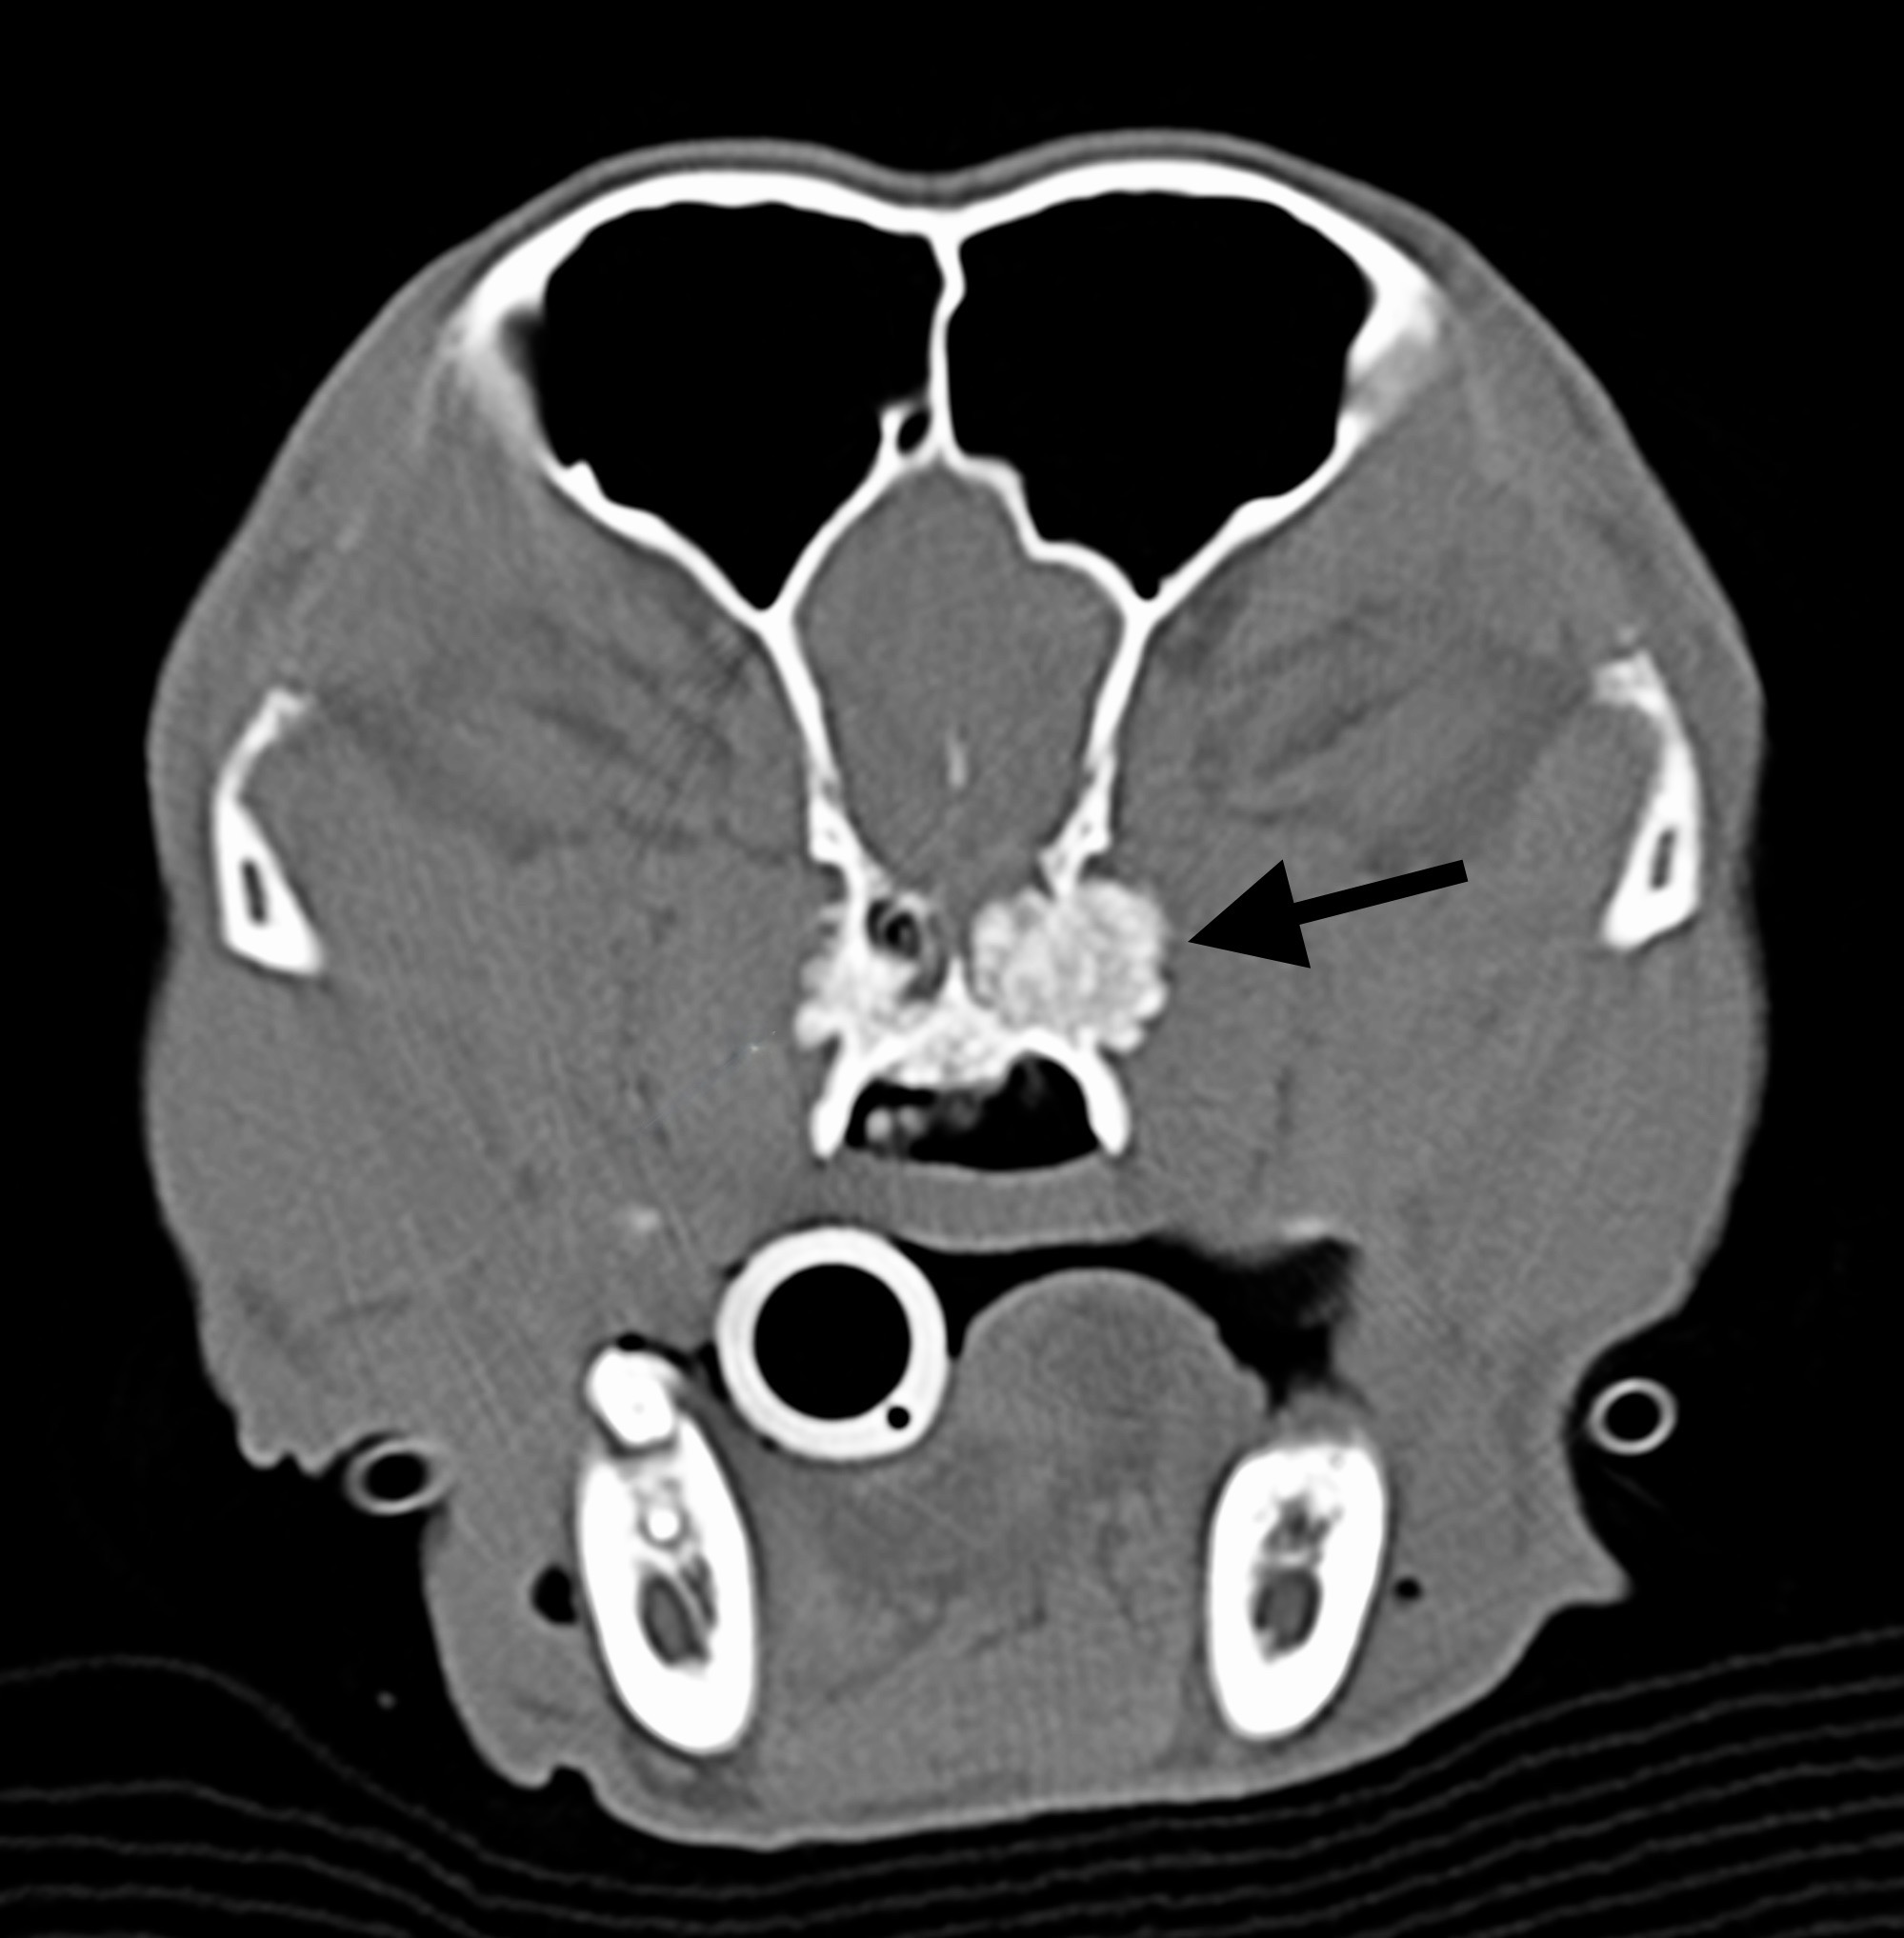

Ci-contre : tumeur dans les cavités nasales d’un griffon présentant une forte gêne inspiratoire depuis quelques jours.